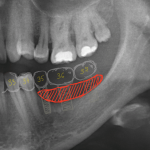

Для примера, давайте рассмотрим вот этот снимок:

Возможна ли имплантация в области левого верхнего премоляра? Вполне. Зуб и гранулему можно удалить, сделать синуслифтинг, вопрос со стабилизацией импланта решить по ходу операции. Остается только один вопрос:

— зачем усложнять?

Другой вариант лечения: удаление зуба, аугментация лунки, через полтора месяца можно приступать к имплантации. Без всяких синуслифтингов и проблем, связанных со стабилизацией импланта. Атрофия альвеолярного гребня? Эта проблема решается на этапе аугментации лунки.